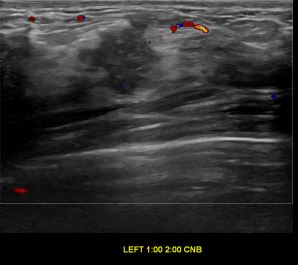

상기환자는 좌측 만져지는 멍우리 있어 검사위해 내원하신 50대 초반

여성분으로 의심스러운 좌측유방혹 조직검사 시행해 침윤성 유방암으로 진단되었습니다